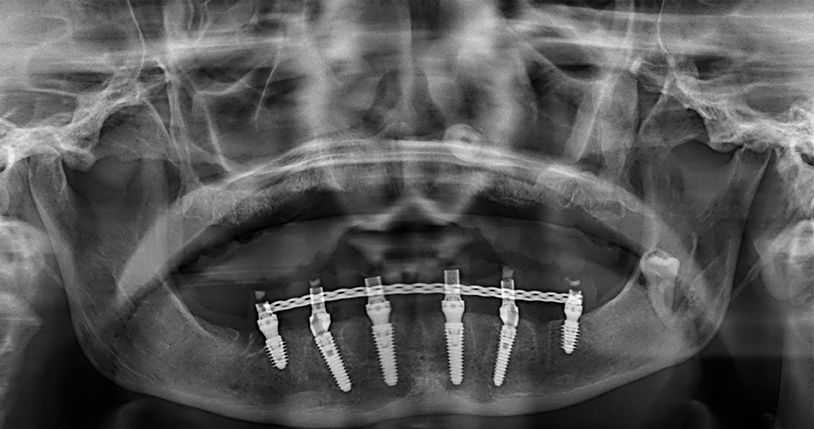

Later, we rehabilitated the mandibular arch with a Toronto prosthesis located on six implants (Fig. 3).

Since her oral hygiene was permanently improved, we decided to reward her by delivering a fixed prosthetic solution immediately loaded on six BLX implants.